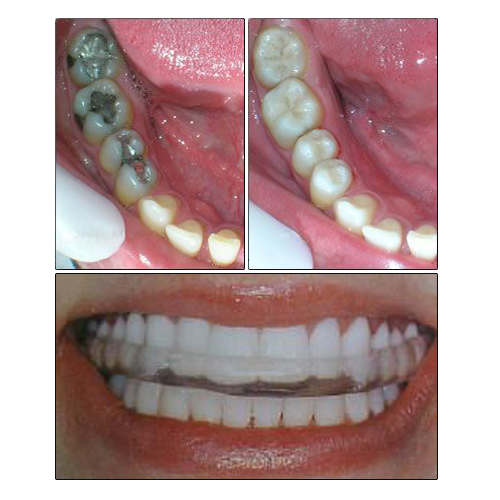

ODONTOLOGIA CONSERVADORA

Recuperamos la anatomía y la función dentaria con materiales libres de metales y altamente estéticos.

ESTETICA

Blanqueamiento dental, frentes estéticos en composite y porcelana.